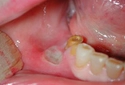

Hamilelik süreci, kadınların fiziksel ve duygusal sağlıkları üzerinde önemli etkiler yaratabilen karmaşık bir dönemdir. Bu dönemde, bazı kadınlar çeşitli sağlık sorunları ile karşılaşabilir. Bu makalede, hamilelikte damak yarası (yarık damak) tedavisinin önemi, nedenleri ve tedavi yöntemleri ele alınacaktır. Damak Yarası Nedir?Damak yarası, doğuştan gelen bir durumdur ve genellikle fetal gelişim sırasında damak bölgesinde meydana gelen anormalliklerden kaynaklanır. Bu durum, damak yapısının tam olarak gelişmemesi nedeniyle ortaya çıkar ve genellikle üst damağın ortasında bir yarık şeklinde görülür. Hamilelikte Damak Yarası NedenleriDamak yarasının oluşumunda çeşitli faktörler etkili olabilir. Bu faktörler arasında genetik, çevresel ve beslenme ile ilgili unsurlar yer almaktadır.

Hamilelikte Damak Yarası BelirtileriDamak yarası, doğumdan önce belirti vermeyebilir. Ancak doğum sonrası bebekte görülen bazı belirtiler, bu durumun varlığını gösterebilir.

Hamilelikte Damak Yarasının Zorluğu

Eda Naz, hamilelik sırasında damak yarası yaşamak gerçekten de zorlayıcı bir durum. Özellikle lezyonların kanamalı ve ağrılı olması, günlük yaşamı ciddi şekilde etkileyebiliyor. Yeme içme sırasında ortaya çıkan ağrılar, annenin beslenmesini olumsuz etkileyebilir ve genel yaşam kalitesini düşürebilir.

Ağız Hijyeninin Önemi

Ağız hijyenine dikkat etmek ve düzenli diş hekimi kontrolleri yapmak elbette önemlidir ancak bu süreçte yaşanan rahatsızlıklar, bu kontrolleri zorlayıcı hale getirebilir. Hamilelik döneminde yaşanan hormonal değişiklikler, ağız sağlığını etkileyebilir ve bu da ek sorunlara yol açabilir.